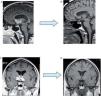

He was asymptomatic until 2006 when he developed facial palsy, dysarthria, diplopia and ataxia suggesting a neurological involvement of sarcoidosis, brain magnetic resonance imaging (MRI) showed infiltration of hypothalamus and peri-chiasmatic region with granuloma and its extension predominantly to right basal ganglia and corpus callosum sub-regions. He was submitted to high dose steroids without possibility of adjustment due to recurrent exacerbations of the disease which led to multiple hospitalizations. Here he was submitted to high dosage of steroids in pulses and in August of 2007 azathioprine (150mg/day) was associated to the 60mg of daily prednisolone.

After six infusions the patient suffered from a decrease of strength in lower limbs leading to frequent falls, apparently with no related of loss of consciousness. The immediate study showed severe hypernatremia (169.7mmol/L), and after a thorough investigation, diabetes insipidus was excluded and the diagnosis of misalignment of the central osmorreceptor secondary to sarcoidosis was accepted. Successful treatment has consisted of daily ingestion of large quantities of water. A repeated brain MRI showed total resolution of the central nervous lesions (Fig. 4B-D).